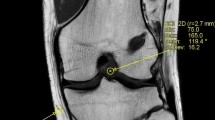

The maturation process of the anterior cruciate ligament autograft exhibits a significant MRI signal change from hypo-intense at (A) 6 weeks postoperatively to more hyper-intense at (B) 3- and (C) 6-months after ACL-R indicating greater disorganization of collagen tissue and higher water content. The MRI signal intensity decreases thereafter at (D) 1- and (E) 2-years post ACL reconstruction to approximate the signal of a native ACL (F). The distal native ACL revealed a more hyper-intense signal compared to the proximal and mid-substance ACL